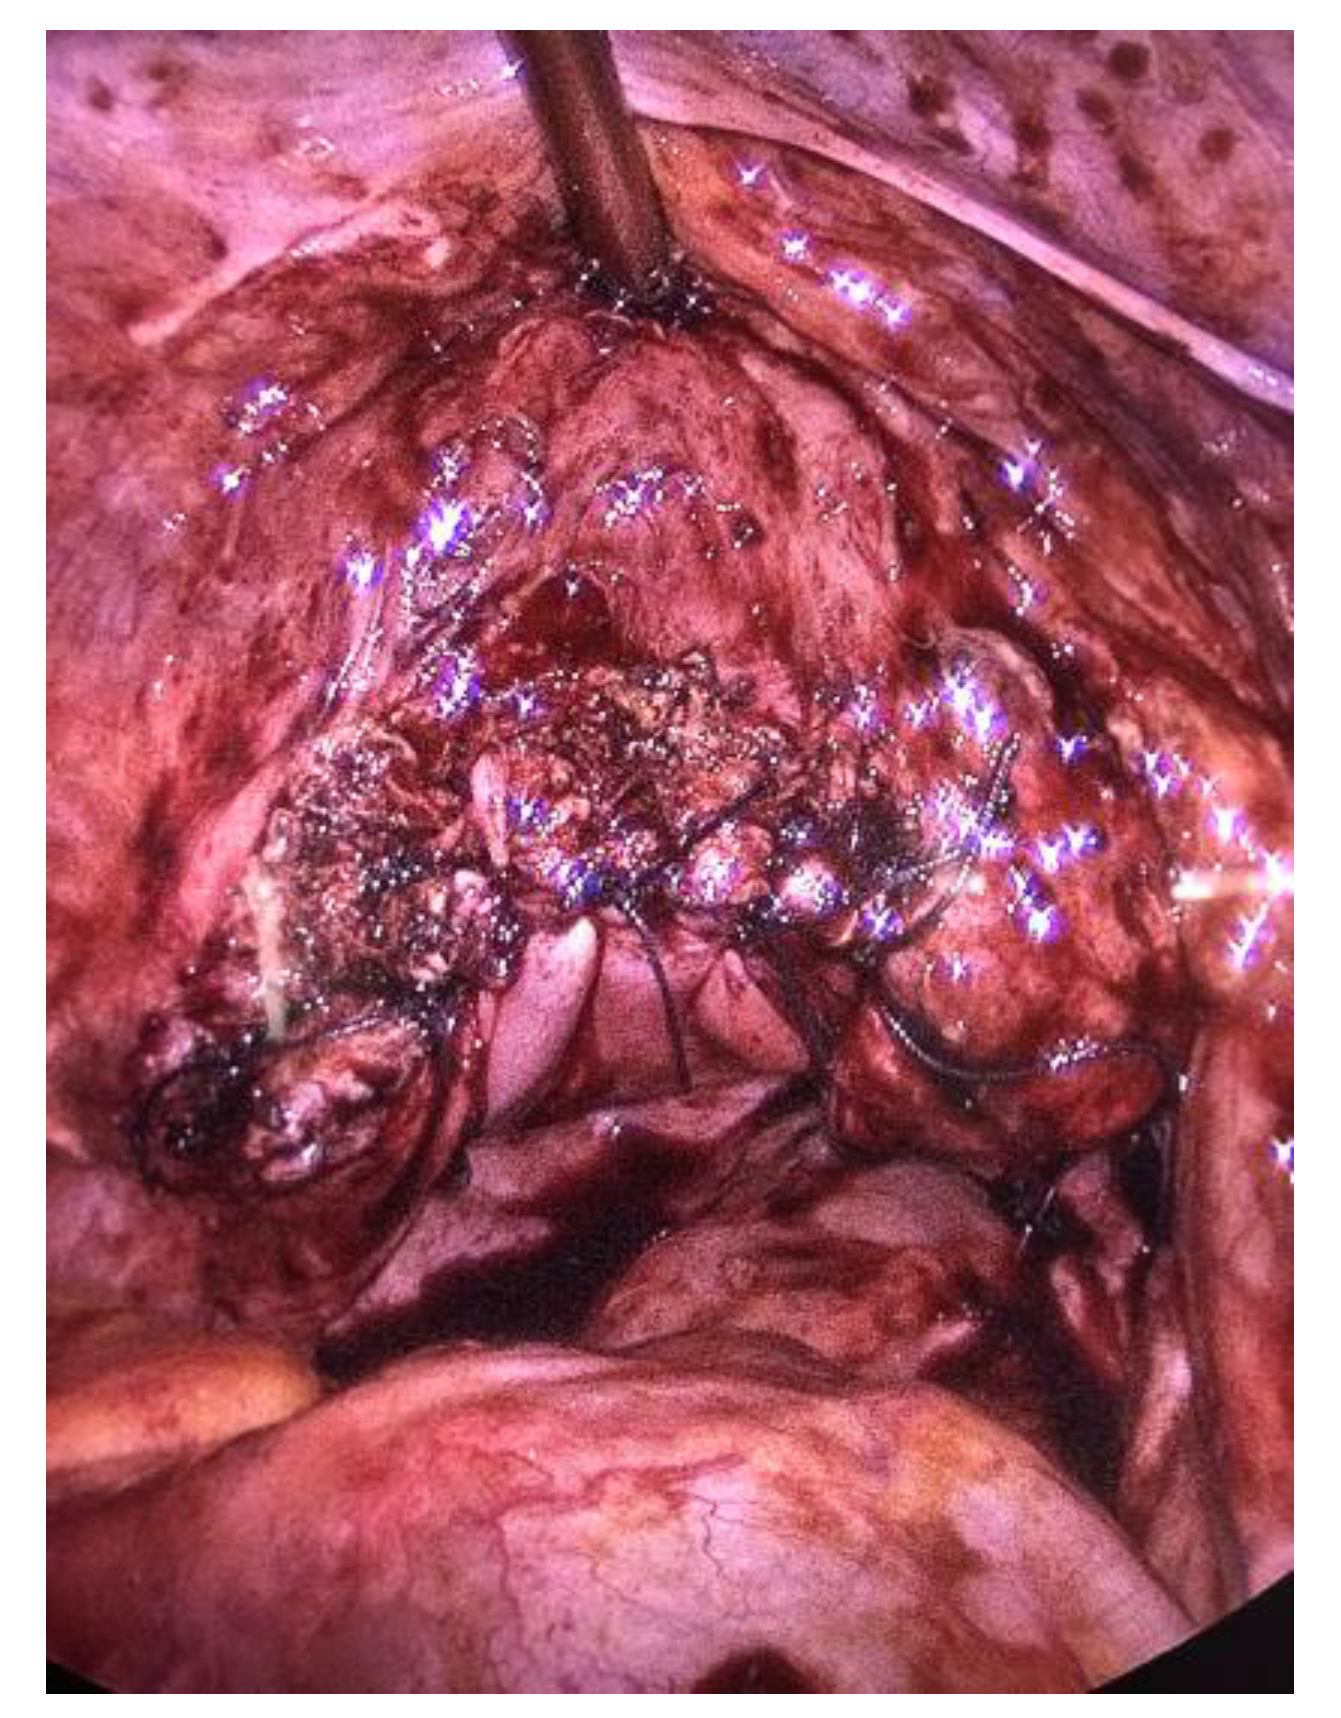

There were no signs of intestinal necrosis, and the vaginal cuff appeared open with signs of fibrosis on the edge (Figure 3). The bladder was filled with methylene blue to allow a clear definition of the bladder limits and a careful dissection was executed. The vaginal cuff edges were trimmed until healthy tissue was seen (Figure 4), then closed by four individual X sutures performed laparoscopically, using Vicryl 1® braided resorbable thread (Figure 5). An intra-abdominal drain was placed.

Figure 3.

Laparoscopic view of the dehiscence, vagina packed with glove.

Figure 5.

Vaginal cuff closed with X-sutures, filled bladder.